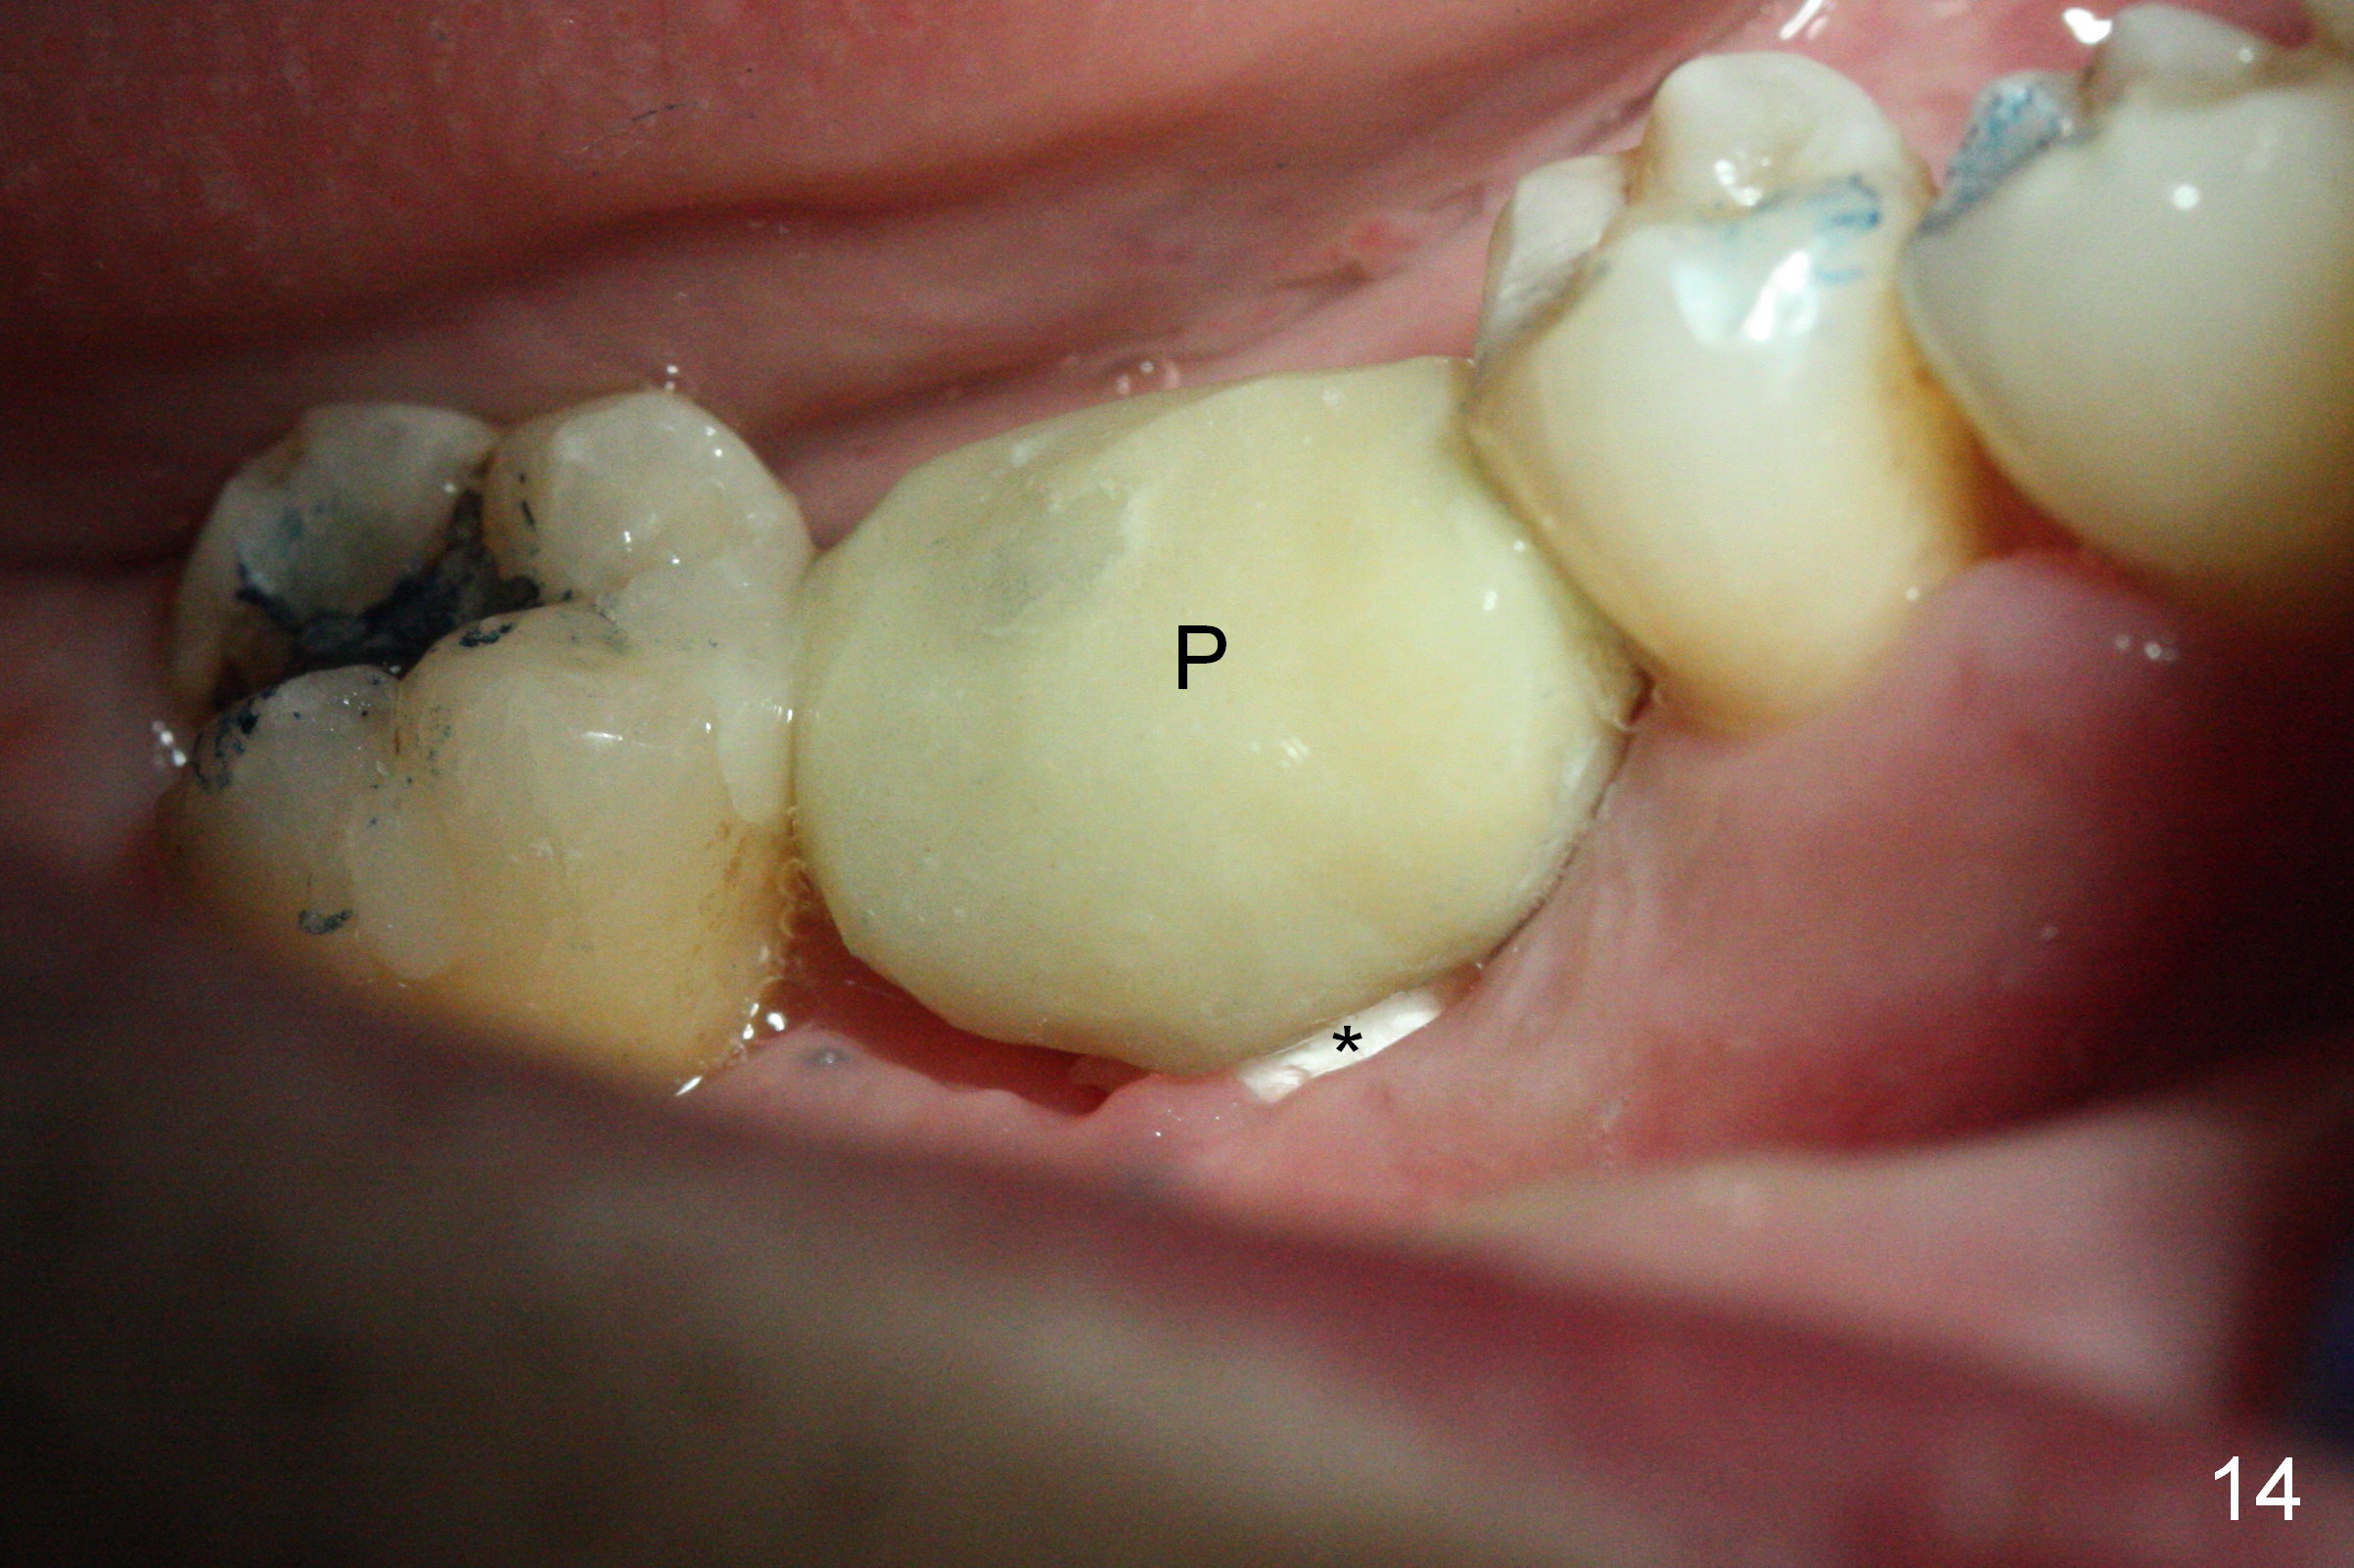

The non-resorbable membrane stays in place 1 month postop (Fig.11 N). When it is removed, the buccal aspect of the cuff of the angled abutment is not covered by bone graft or granulation tissue (Fig.12 C). In fact, the membrane does not hold the bone graft in place as effectively as a provisional. The space is filled with a piece of gauze (Fig.13) while the abutment is reduced for provisional and MO composite at #31 is placed. Before seating the provisional (Fig.14 P), a piece of collagen plug is inserted into the space (*) after removal of the gauze.